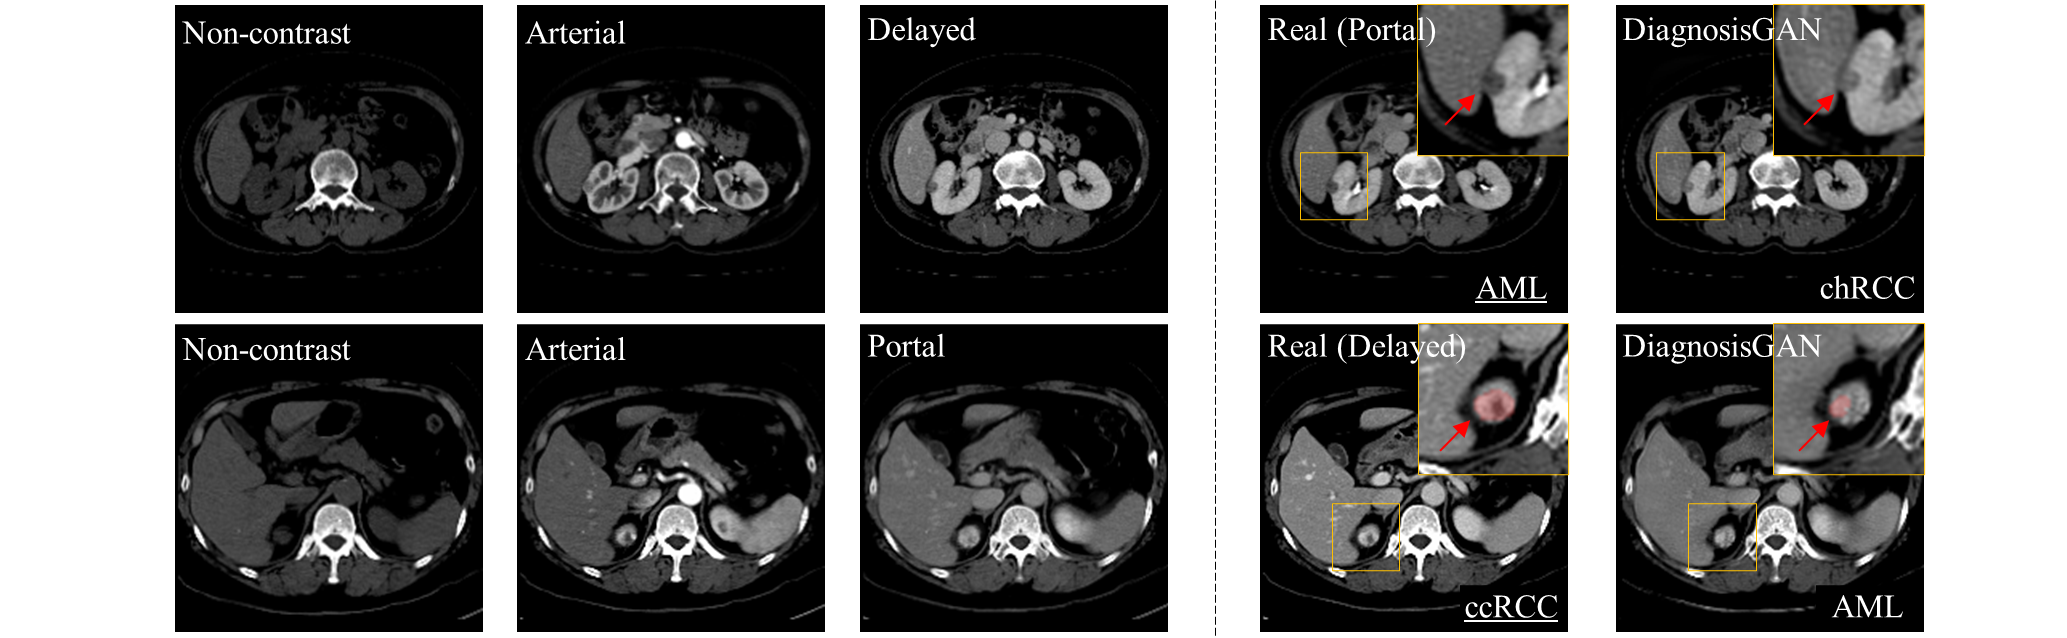

Refer to caption

Figure 5: Qualitative comparison. Tumor regions are zoomed-in and indicated by red arrows. The actual cancer subtype labels are shown in the real image. The predicted subtype class using the completed four-phase CT is displayed on each result, where the correct labels are underlined.

Fig. 5 shows several examples where the proposed DiagnosisGAN leads to correct cancer subtype classification. Here we present example results from BaseSyn, CollaGAN, Syn-Seg, ReMIC, and DiagnosisGAN for different missing phase cases. For each case, the true cancer subtype label is shown in the real image. The tumor areas are zoomed in for more details. We predict the cancer subtype probabilities p^^𝑝\hat{p} from the completed four-phase CT m+superscriptsubscript𝑚\mathcal{I}_{m}^{+} using the classifier C𝐶C, and the subtype class having the highest probability in p^^𝑝\hat{p} is displayed in each synthesized result I^msubscript^𝐼𝑚{\hat{I}}_{m}. As can be seen, with the synthesized images of DiagnosisGAN, the cancer subtypes are correctly classified in all cases, while CollaGAN and Syn-Seg lead to misclassification in several cases. For example, in the case of synthesizing portal phase (the first two rows), BaseSyn, CollaGAN and ReMIC misclassify the cancer subtypes as ccRCC, where the true label is AML, while DiagnosisGAN yields the accurate subtype prediction result. We can see that the tumor regions synthesized by DiagnosisGAN have a similar visual appearance to that of the real images, while the results of the baseline methods show different image characteristics around tumor regions, such as intensity and contrast, and contain some artifacts that are not present in the real images. It has to be noted that it is nontrivial to judge the diagnostic usefulness of the synthesized CT images solely by visual inspection since renal tumors exhibit subtle differences in image features across cancer subtypes, leading to inter-observer variability [47, 62]. However, we can clearly see that synthesizing missing phases by using DiagnosisGAN is beneficial for the cancer subtype classification of hard samples, which are misclassified by the baselines. We also visualize some failed cases in Fig. 6. For the top example in Fig.  6, the size of the renal mass is 1cm, which is too small to accurately differentiate tumor subtypes in CT. The true subtype of tumor is AML, but it is misclassified as chRCC by our method. Besides, for the bottom example, the inaccurate segmentation of tumor boundaries could cause misclassification, but this issue can be alleviated by performing further refinement process.